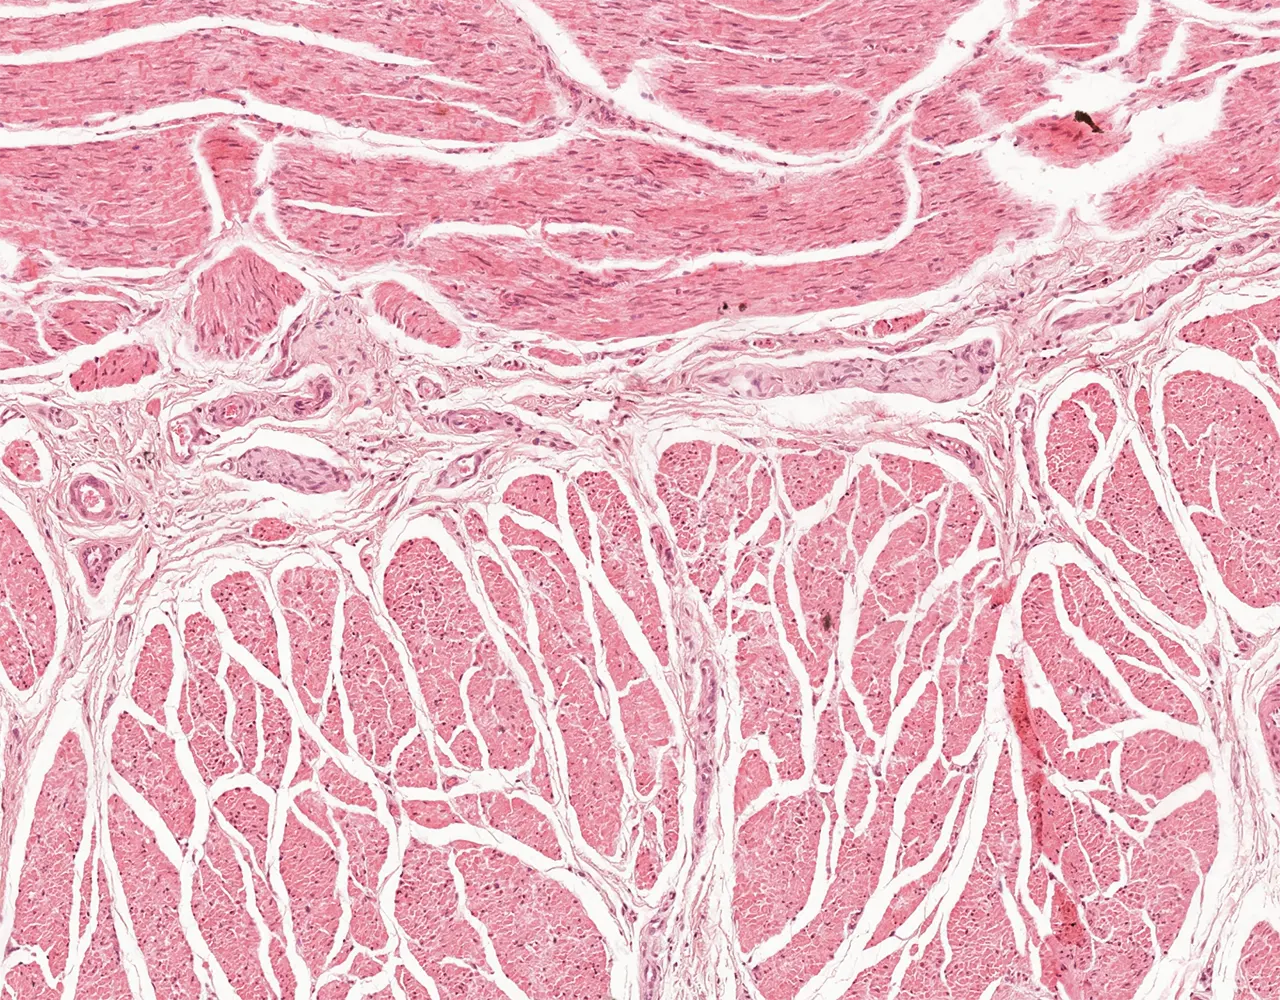

- Microscopically, the esophagus is composed of four layers: mucosa, submucosa, muscularis propria, and adventitia.